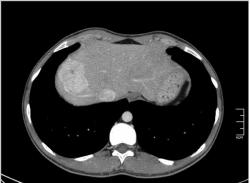

КТ печени. Наблюдения для размышления.

Уважаемые коллеги, особенно врачи КТ. Надеюсь что данная публикация окажется полезной для многих из Вас. Ниже представлены сканы печени; предлагаю Вам ознакомится с ними и высказать свое мнение. Пациент мужчина средних лет, специфичных жалоб не предъявляет.

Евгений: В принципе похоже, весьма может быть. Тогда это простая инциденталома, т.е. находка не имеющая значения. А КТ с контрастом, обратите внимнаие на контрастированные гиперденсные печёночные вены.

Уважаемый v1tal! Огромная Вам благодарность; Вы назвали ключевое слово: фаза! Высказанная Вами мысль, это моя основная цель данной публикации. Постараюсь позже более детально объяснить почему. Представленные сканы выше, были выполнены на стандартной портальное фазе. А сейчас, я покажу сканы данного пациента выполненные на артериальной фазе :

Это может быть нодуллярной гиперплазией? Еще бы рубец законтрастировался в отсроченную фазу.

Да Ola la, Вы абсолютно правы; это Фокальная Нодулярная Гиперплазия печени (FNH Focal Nodular Hyperplasia). Одна из немногих гиперваскулярных опухолей печени. Наверное некоторые коллеги спросят, и зачем было изначально публиковать портальную фазу, на которой «не видно» (хотя опухоль видна, пусть и не напрямую, и Nela это доказала); и только потом показывать сканы на артериальной фазе, на которой всё «красиво и показательно». Постараюсь объяснить.